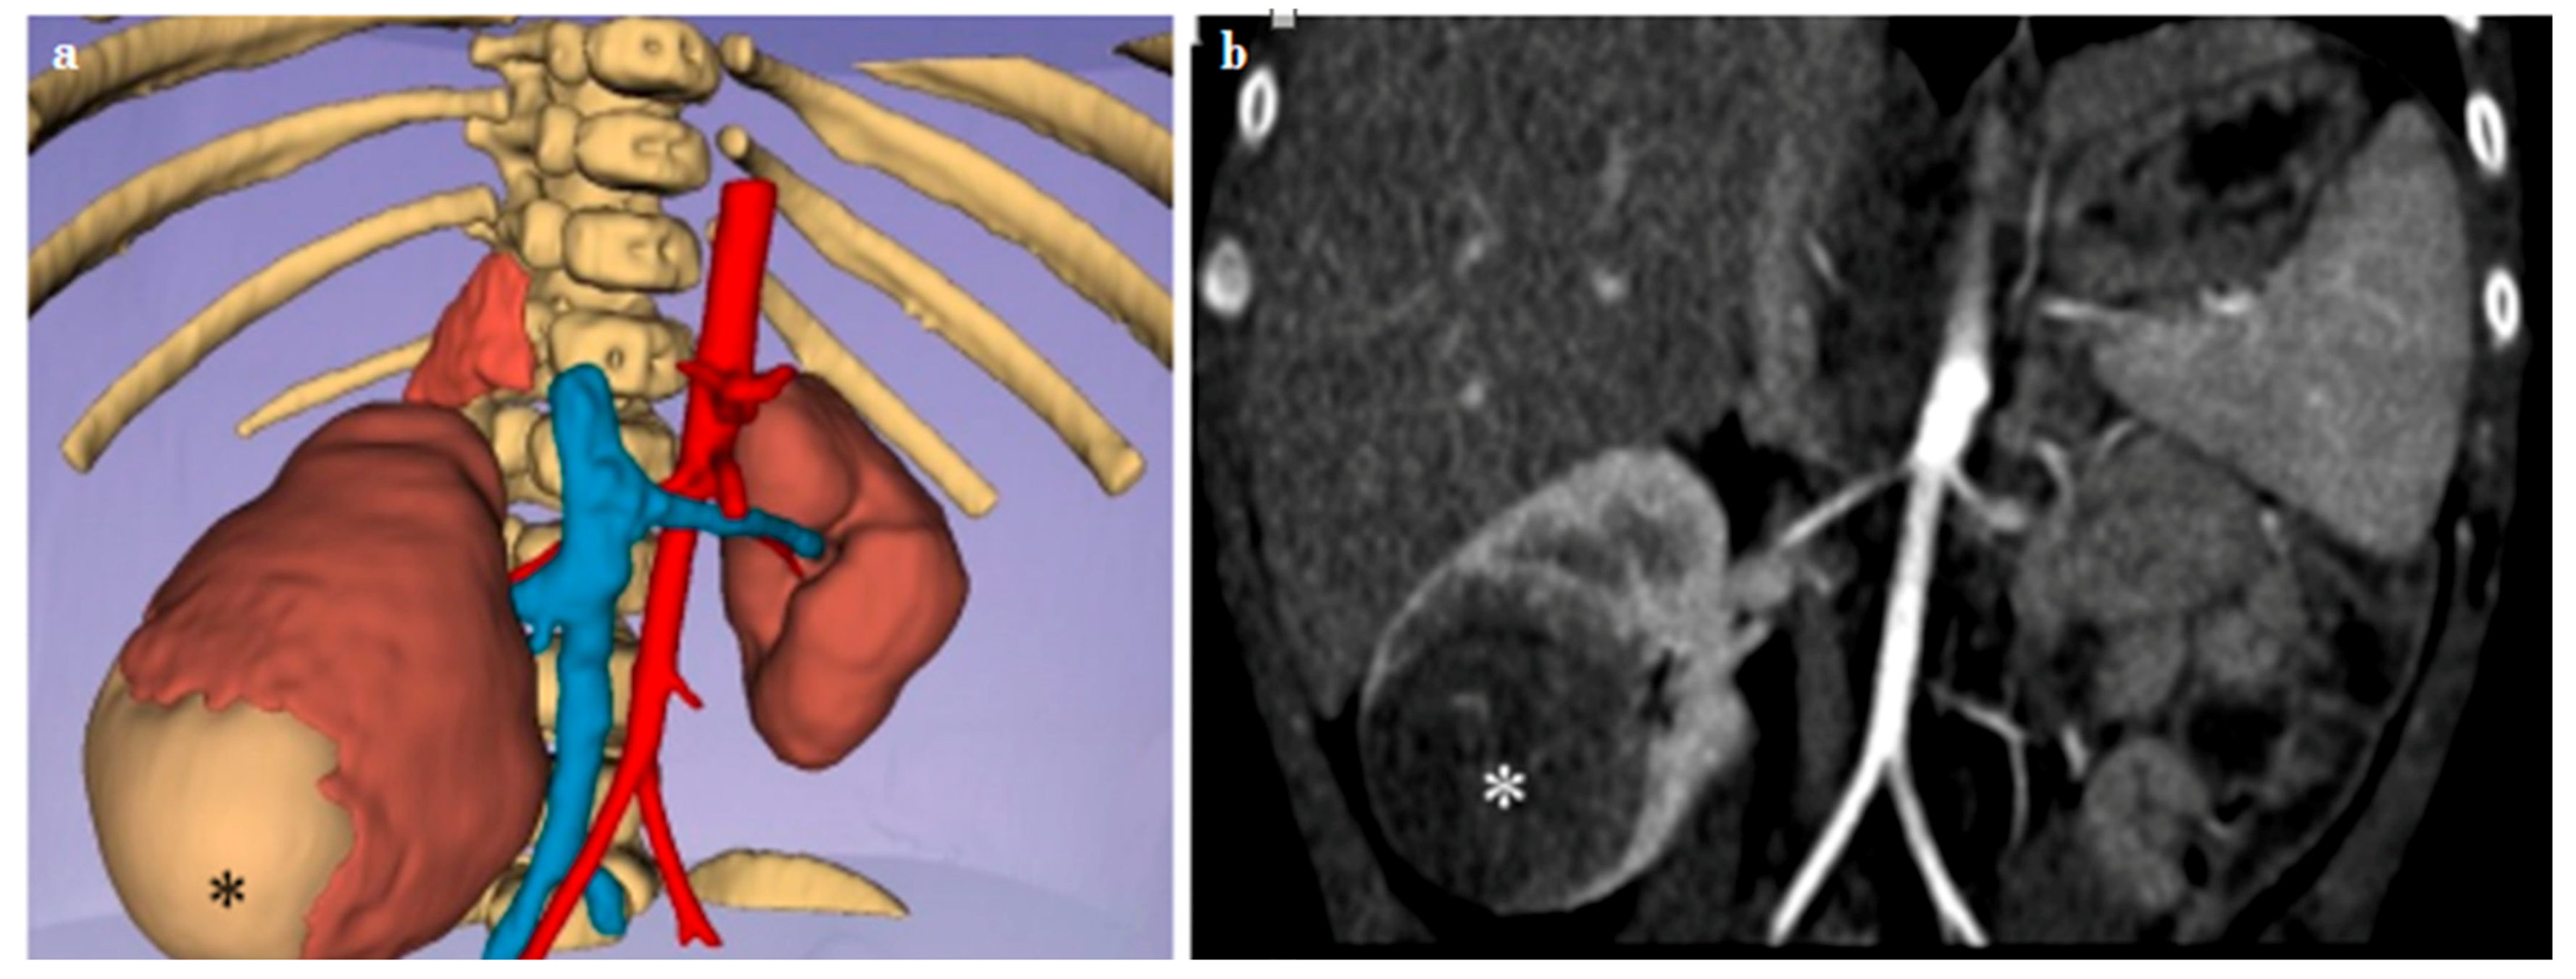

3.2. Adrenal Lesions

| Case n. 1 | Female | 4 years | Neuroblastoma | Left |